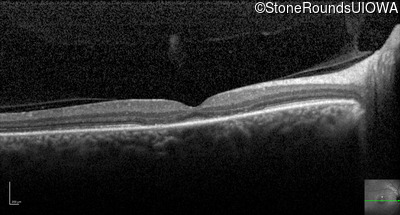

Optical Coherence Tomography - Right - 20/50 -1 sc

Exemplar / OCT Stack